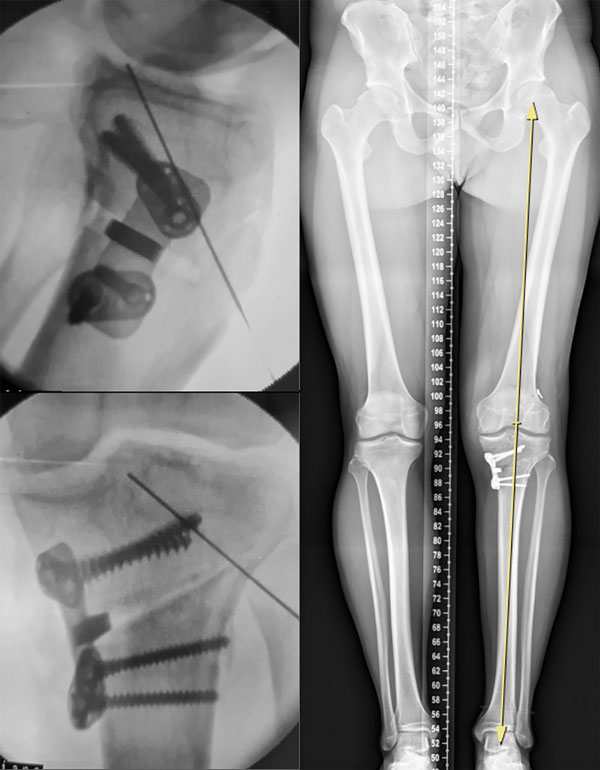

Se solicitó una radiografía panorámica de ambos miembros inferiores junto con radiografías de frente y perfil de ambas rodillas y axial de ambas rótulas (fig. 1). El eje mecánico se representó con una línea que va desde el centro de rotación de la cabeza femoral hasta el centro del domo astragalino.9 Dicho eje se calculó según el porcentaje del ancho de la meseta tibial en la cual el eje la atraviesa: 0% en el borde medial y 100% en el borde lateral. Se calificó deseje en varo cuando dicho eje se situó medial a la espina tibial medial o a más del 41% de la meseta tibial10 (ver fig.1).

La planificación preoperatoria para la osteotomía valguizante de tibia para pacientes con artrosis del compartimento medial tiene como objetivo restablecer el eje mecánico mediante la corrección en el vértice de la eminencia tibial lateral, coincidiendo con el 56% de esta. El ángulo de corrección requerido en el plano coronal se calculó trazando una línea desde el centro de la cabeza femoral hacia el vértice de la espina tibial lateral y otra línea desde el centro de la cúpula astragalina hacia el mismo vértice. El ángulo formado por su intersección representa el ángulo de osteotomía de apertura necesario para corregir el deseje. Este ángulo se transpone a la ubicación del corte más lateral de la osteotomía planificada en la tibia proximal y se expande a la tibia proximal medial. Esta angulación calculada crea un triángulo, con la altura (en milímetros) en la cortical tibial medial que representa la cantidad necesaria de corrección para la osteotomía9 (ver fig.1).

Figura 1: Planificación radiográfica. A) Eje mecánico en varo. B) Radiografía de rodilla frente. C) Radiografía de rodilla de perfil. D) Planificación de osteotomía con corrección de 5°.

Se ubicó al paciente en decúbito supino bajo anestesia regional y general y manguito hemostático a 300 mmHg. Por artroscopía exploratoria mediante portales parapatelares medial y lateral se identificó lesión del menisco interno con degeneración del cartílago articular. Se limpió el compartimento con punta de shaver. Las lesiones asociadas fueron tratadas de manera concomitante. Posteriormente se realizó un abordaje anteromedial de aproximadamente 8 cm entre la tuberosidad anterior de la tibia (TAT) y el borde cortical posteromedial sobre los isquiotibiales (pata de ganso). Disección por planos hasta llegar al hueso. Se identificaron y repararon el tendón rotuliano y el ligamento colateral medial (LCM). Divulsión posteromedial subperióstica por debajo del LCM superficial y la musculatura poplítea. Se colocaron dos clavijas a nivel metafisario con dirección cefálica hacia la cabeza del peroné mediante guía radioscópica, verificando una adecuada inclinación tibial (slope tibial) en la proyección de perfil. Se tomó el recaudo de dejar 1.5 cm de distancia entre la osteotomía y el cartílago articular para permitir una adecuada fijación de la placa de osteosíntesis y, al mismo tiempo, evitar una fractura intraarticular. Con una sierra oscilante se ejecutó la osteotomía desde la corteza medial siguiendo como referencia la guía de ambas clavijas. La corteza posteromedial y el avance hacia la cortical lateral se terminó con escoplos laminares, teniendo el recaudo de dejar al menos 1 cm de cortical intacta que actúe como bisagra de la osteotomía. Es importante recalcar que esta debe abarcar los dos tercios posteriores, dejando el tercio anterior intacto para la segunda osteotomía ascendente en el plano coronal sobre la TAT (técnica biplanar). Una vez hechos los cortes, se utilizó un distractor de espinosas en la cortical medial, generando la apertura de la osteotomía hasta conseguir la altura en milímetros deseada y planificada en el preoperatorio. Se introdujo la cuña de hueso tricortical del banco de huesos (previamente medida y trabajada en una segunda mesa quirúrgica). Osteosíntesis del constructo con una placa de tibia proximal bloqueada (fig. 6).

Figura 6: Imagen intraoperatoria de la osteotomía valguizante de tibia y escanograma postoperatorio al año. Nótese la corrección del eje mecánico.